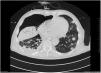

The chest-CT scan showed an extensive right lung consolidation and bilateral nodular consolidative foci (Fig. 1). Empiric liposomal amphotericin B was added to improve fungal coverage. A bronchoalveolar lavage (BAL) was performed. Multiplex PCR for respiratory viruses and bacteria (influenza, respiratory syncytial virus, CMV, adenovirus, coronavirus, rhinovirus, Legionella, Mycoplasma, Chlamydia, Escherichia coli, Klebsiella, Moraxella, Serratia, S. aureus, S. pneumoniae) were negative. No acid-fast bacilli were observed in the auramine stain. On direct examination with Gram and Calcofluor stain of the BAL a microorganism compatible with C. posadasii was found, and later confirmed on cultures (Figs. 2 and 3). The patient continued to require high oxygen requirements and eventually developed multiorgan failure. Nine days after admission the patient died. On the necropsy, spherules full of endospores were found within the pulmonary parenchyma, confirming an invasive fungal infection (Fig. 4).